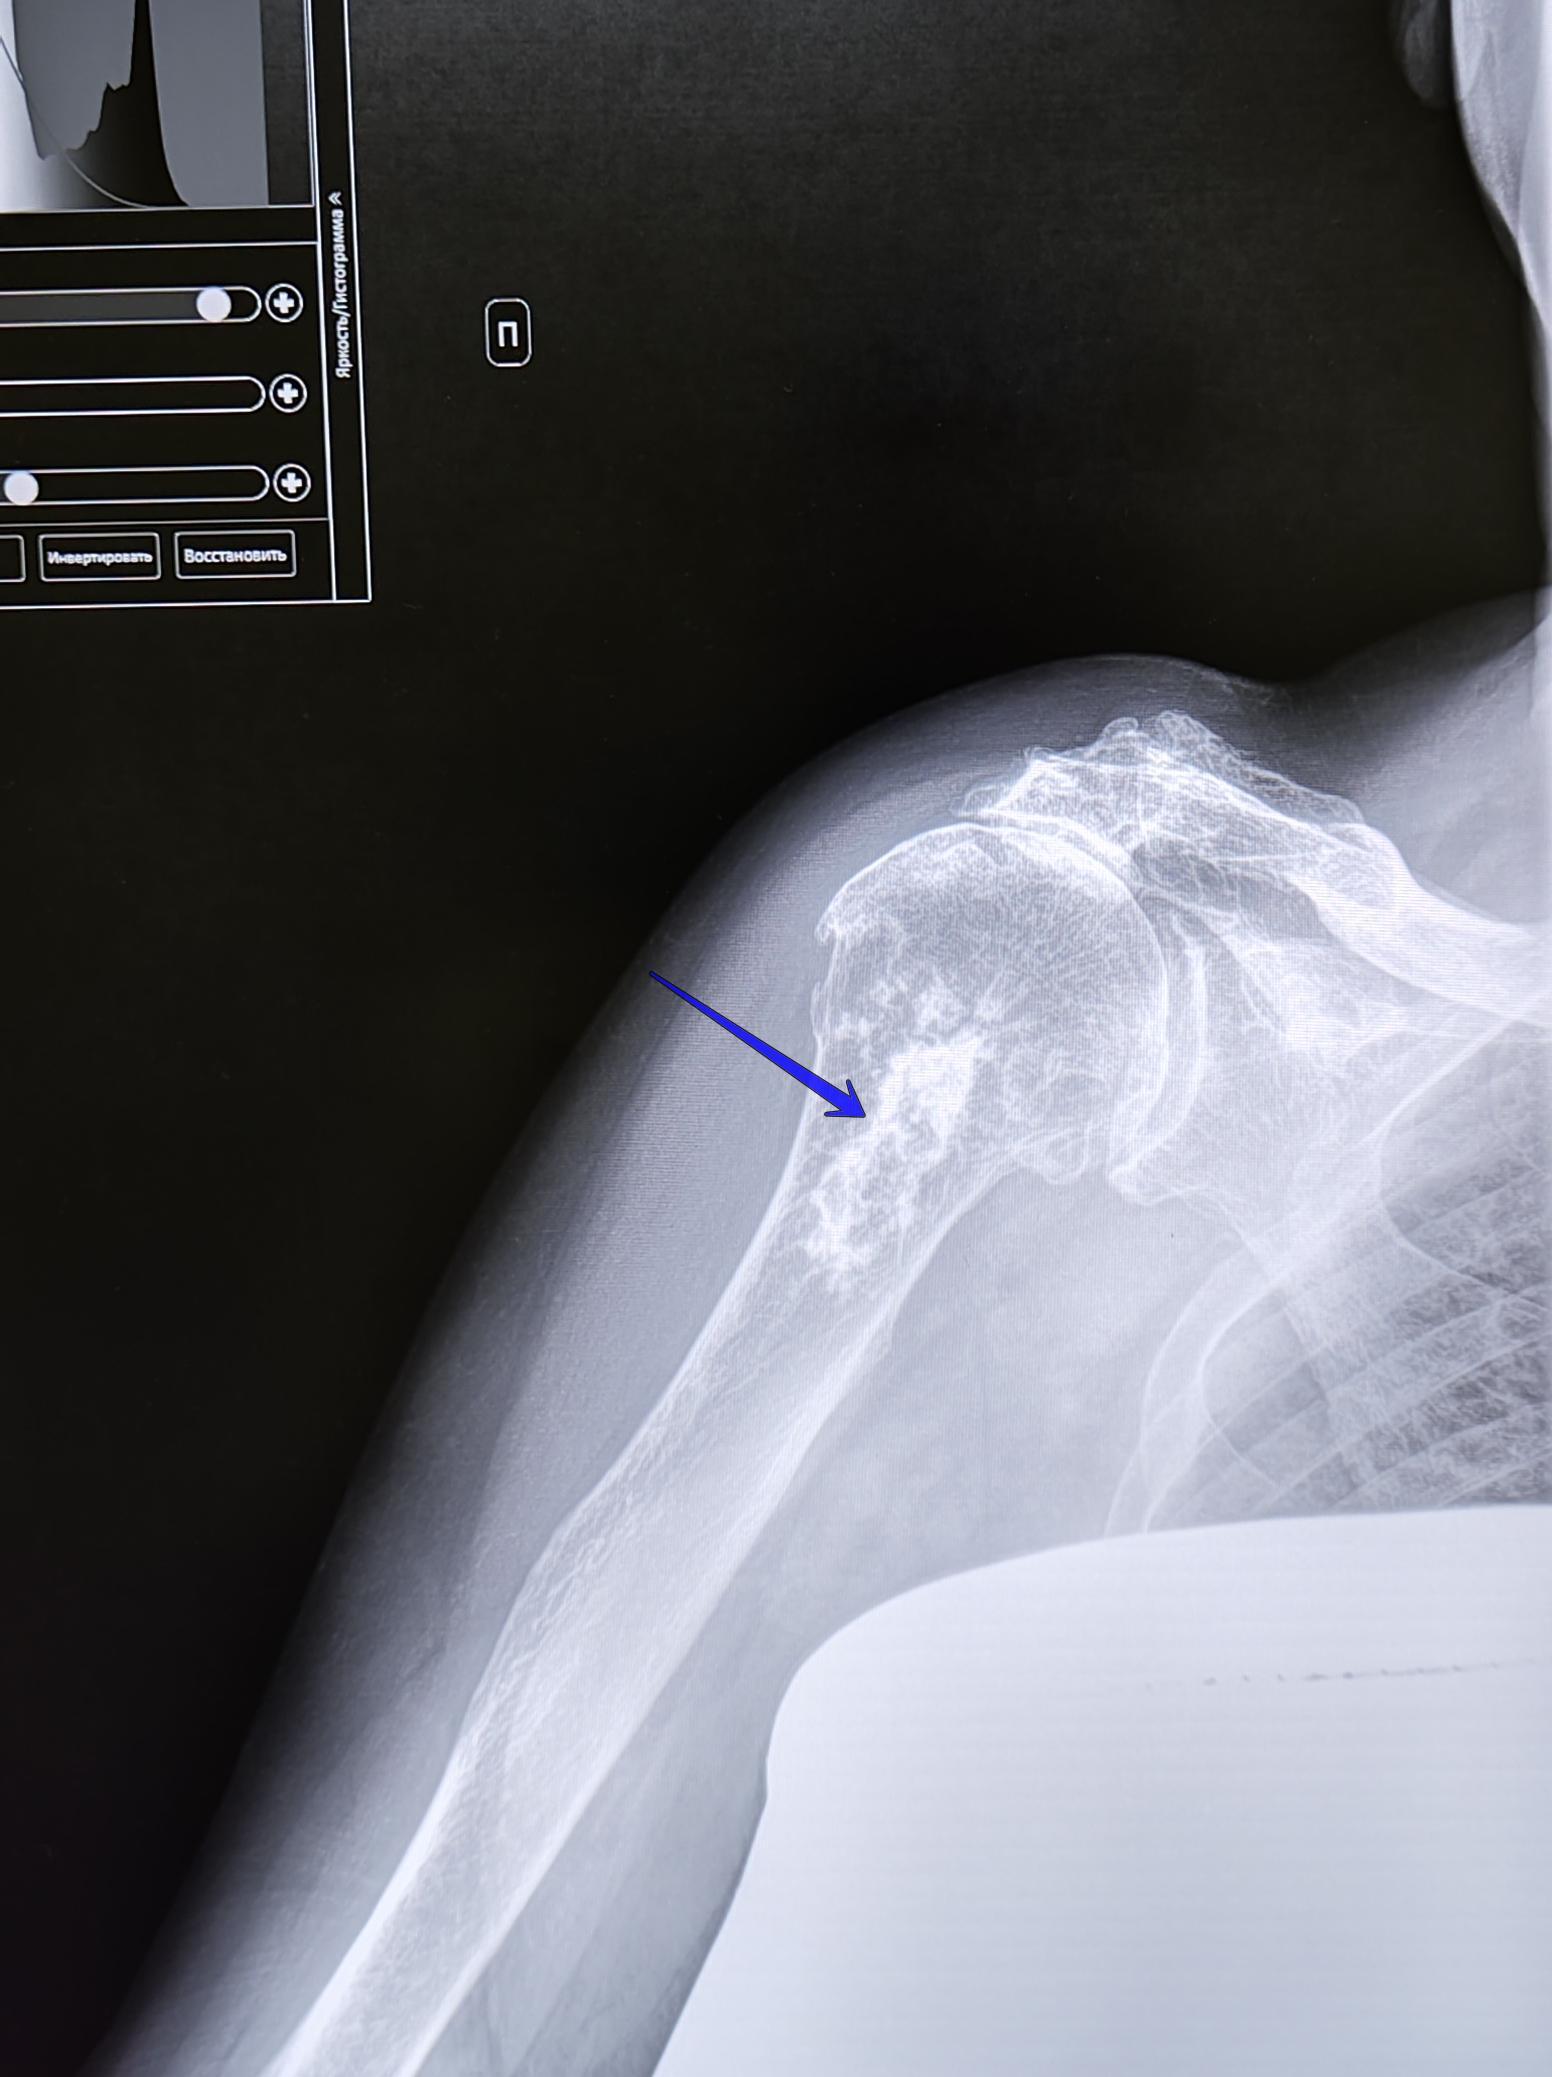

Энхондрома плечевой кости

Снимок пациентки 70 лет.

Описание снимка: на Р-грамме правой плечевой кости-в проксимальном метадиафизе плечевой кости, визуализируется образование размером 11х3.6 см, неправильной овальной формы, с четкими фестончатами границами, с участками кальцификации. Надкостница не изменена, периостальная реакция -отсутствует, окружающие мягкие ткани-не изменены. Неравномерное сужение щели плече-лопаточного сочленения, АКС, субхондральный склероз, краевые остеофиты, значительное сужение субакромиального пространства, уплотнение нижней поверхности акромиона. Заключение: Образование правой плечевой кости(энхондрома).ДОА плечевого сустава 2ст., АКС 2ст.Косвенные признаки импиджмент синдрома правого плечевого сустава. Рек-но: конс. онколога, травм.-орт.

Окончательная верификация: добро/зло-по результатам гистологического исследования.